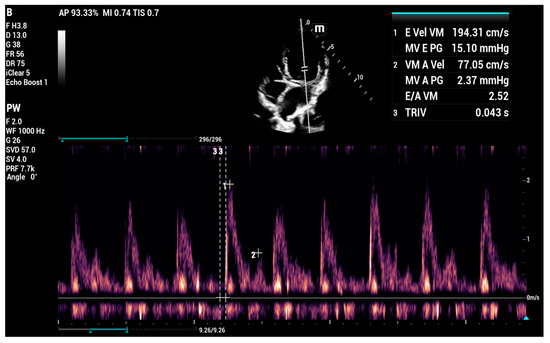

4.8.5. Vmax Wave E

4.8.6. E-Wave Deceleration Time